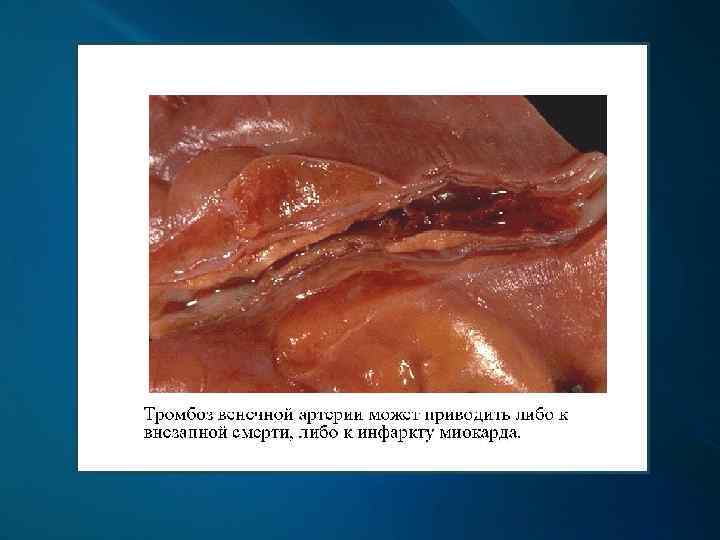

Венечная артерия на поперечном срезе с различной степенью атеросклеротического стеноза на разных участках

Инфаркт миокарда - очаг некроза, возникший вследствие острого несоответствия между потребностью миокарда в кислороде и доставкой его по коронарным артериям. Зона некроза при инфаркте пространственно увязана с бассейном конкретной артерии.